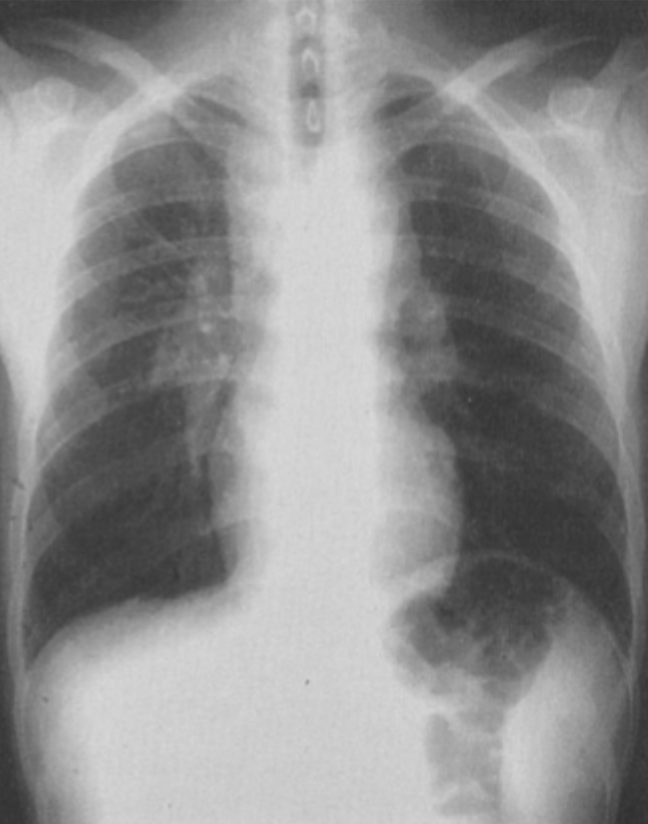

10

Q

What is this ?

A

Bilateral hilar lymphadenopathy